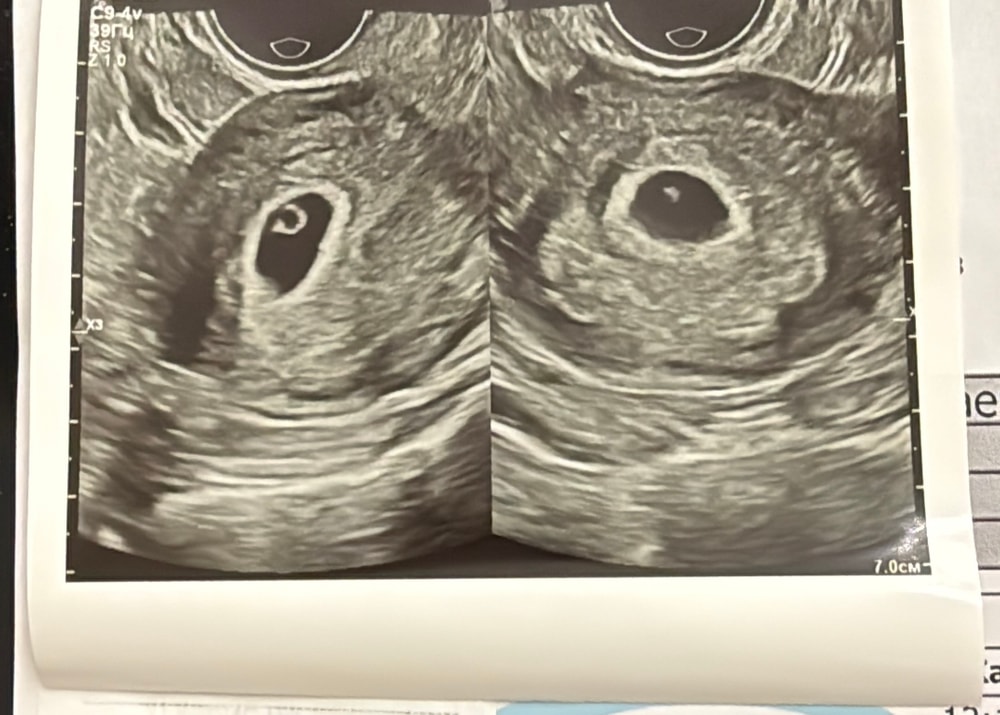

Трижды мама, а теперь засомневалась даже в измерениях прошлых. Они померила по одному диаметру и написала пя 12 мм, а оно вытянутое немного у меня....а вчера как раз измеряла по 3 показаниям и выводила средний.... Я думаю тут тоже сыграло роль определенную. И не видно даже жм на фото Изображение

Людмила Хасанова, ИзображениеВо втором якобы эмбрион, но он совсем маленький. Через живот ничего не было видно, потом вагинально посмотрела.